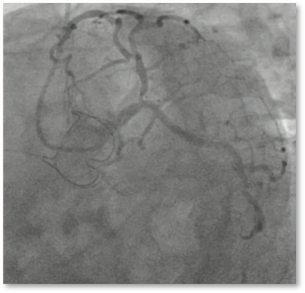

Left Main Bifurcations

Live Case Series

LEFT MAIN BIFURCATION

& Aorto Ostial Disease